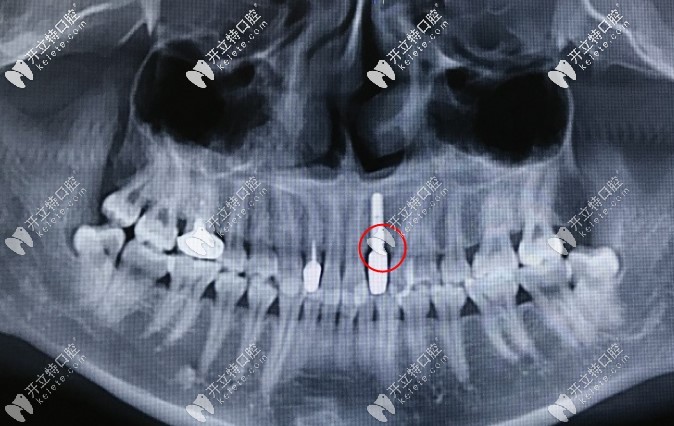

種植牙3年骨吸收的CT▼

諾貝爾Active種植體可以預(yù)防種植牙骨吸收情況發(fā)生